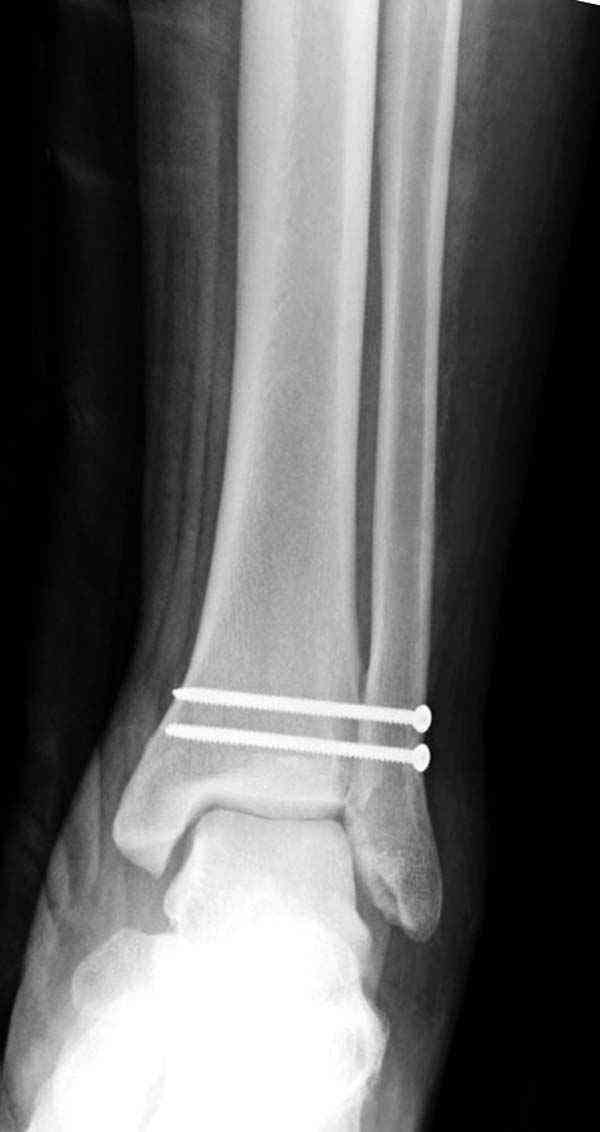

Нет первичных снимков, перелом очень низкий и под большим сомнением диагноз разрыва синдесмоза. Медиальная сторона отрепонирована на "хорошо" и, по-видимому, прорезание проволоки произошло во время операции. Без снимков трудно судить о высоте малоберцовой, а лодыжка находится в варусе. Лагирование получилось, но возле тонких шурупов передне-задний шуруп выглядит немного тяжеловато.

Медиальная лодыжка фиксируется каннюлированными лодыжечными шурупами перкутанно, а неточная репозиция (интерпозиция) является показанием к открытой технике. При больших вертикальных фрагментах нужны противоскользящие медиальные пластины.

Здесь несколько частных случаев: перелом голеностопа со сравнительными снимками и разрыв синдесмоза, а также медиальная Hook пластина.